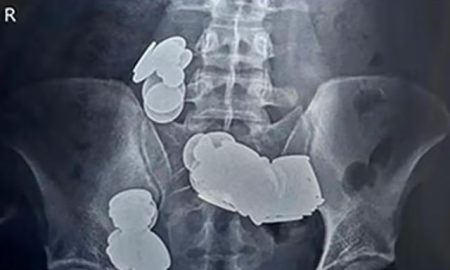

Riječ je o pacijentu sa psihoemocionalnim poremećajem.